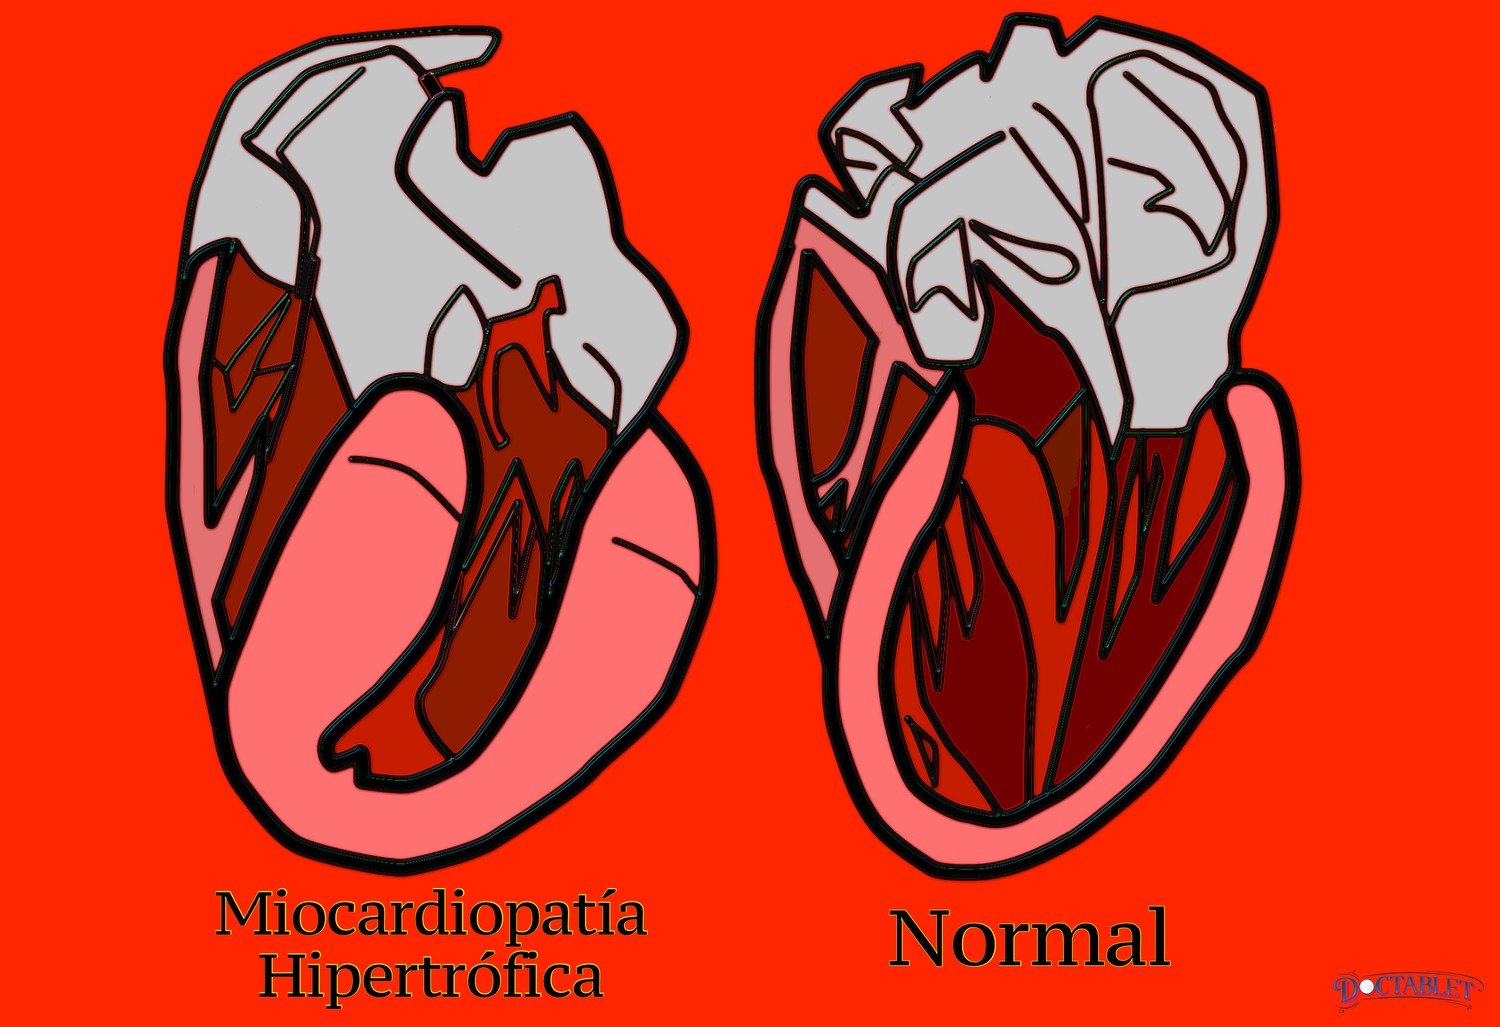

Si miramos bajo microscopio el músculo cardíaco de un paciente con MCH, veremos células muy diferentes a aquellas que hay en el corazón de una persona sana. Se pierde la estructura organizada del músculo, por lo que las células se ven raras y como en caos. El tipo de músculo formado por estos genes mutados es anormal de diferentes maneras. El músculo anormal es más grueso que el músculo cardíaco normal. Además, las funciones de un músculo cardiaco normal (tales como apretar y relajar), pueden verse alteradas. El músculo cardíaco anormal también puede ser "arritmogénico", esto significa que puede desencadenar espontáneamente una arritmia peligrosa en el corazón.

Varias regiones del corazón pueden presentar fibras anormalmente gruesas. La ubicación del músculo anormal dentro de la estructura del corazón afecta cómo la MCH se siente para la persona que lo tiene. Si sucede que esta musculatura anormal está localizada en el lugar donde la sangre sale hacia el cuerpo, las fibras pueden hacer que este canal sea más estrecho. Esta condición se llama "cardiomiopatía hipertrófica obstructiva"

Estas fibras también pueden aparecer en la parte superior (ápice) del corazón. El ápice del corazón es la palabra que usan los médicos para describir el cono final del ventrículo izquierdo. La cardiomiopatía hipertrófica apical primero fue descrita en Japón y aveces se le llama la variante japonesa. La MCH se puede dar de otras maneras. Las diferentes paredes del corazón pueden desarrollar musculatura gruesa o grasosa. Hasta cuando no obstruye el flujo de sangre, la MCH puede causar problemas. Un corazón excesivamente grueso pierde muchas de sus capacidades normales, como la de impulsar sangre hacia afuera (sístole) y la de relajarse a sí mismo para llenarse de sangre. Algunos pacientes de MCH pueden sufrir de insuficiencia cardíaca porque el corazón anormal no puede cumplir con los requisitos que tiene el cuerpo.